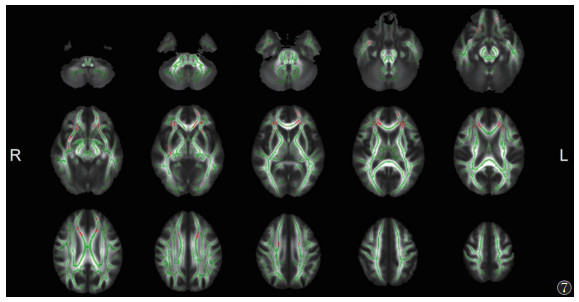

与EMTB组相比,ITB组脑白质显示出较广泛的FA降低和MD升高(P<0.05,TFCE和FWE校正)(图 5,6),其范围小于ITB组与HC组之间的差异。其中胼胝体膝部、双侧前放射冠等同时出现FA降低和MD升高(图 7)。

![]() |

| 注:与EMTB组相比,ITB组脑白质FA降低和MD升高的重叠区域显示为红色(P<0.05,TFCE和FWE校正)。脑白质骨架显示为绿色。L,左;R,右 图 7 ITB组与EMTB组FA、MD的差异重叠区域 |